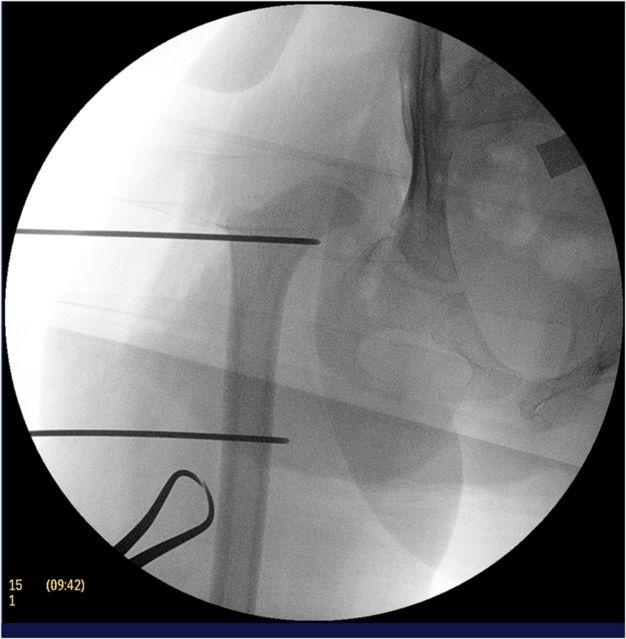

A combined procedure including open reduction, femoral shortening osteotomy, and an acetabular procedure is often necessary to obtain a desirable result in children of walking age who have a high-riding hip dislocation.

STEP 2 EXPLORE THE HIP JOINT: Make sure to find the true acetabulum and remove all obstacles to femoral head reduction.

STEP 3 FEMORAL HEAD REDUCIBILITY: Check the reducibility of the femoral head in different positions through a full range of hip motion.

步骤2 探查髋关节:务必找到真正的髋臼,并清除股骨头复位的所有障碍。

步骤3 股骨头可复性:通过全范围的髋关节活动,检查股骨头在不同位置的可复性。